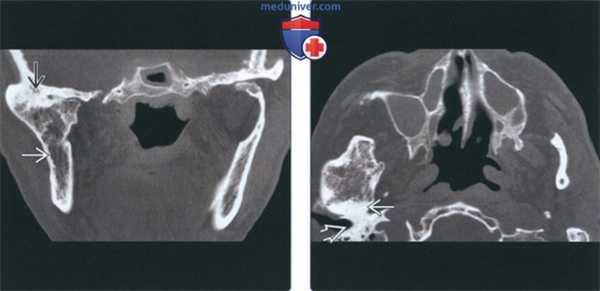

(Слева) На корональной КТ без КУ у этого же пациента определяется выраженное увеличение правого мыщелка, соединенного с височной костью костным мостиком с наружной стороны. Суставное пространство облитерировано. Шейка мыщелка и ветвь нижней челюсти утолщены.

(Справа) На аксиальной КТ без КУ у этого же пациента определяется склероз и увеличение всех размеров мыщелка со слиянием с височной костью. Суставное пространство не визуализируется.